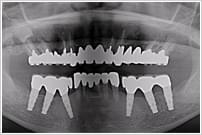

症例の紹介

58歳 男性

多数歯欠損。全歯におよぶカリエス。

右下6・7番、左上4・5番を抜歯。

右下6・7番、左上4番、左下3・4・6・7番をインプラント。

全体に歯周治療。

全顎のカリエスは審美性を考慮して、陶材焼付冠で補綴。